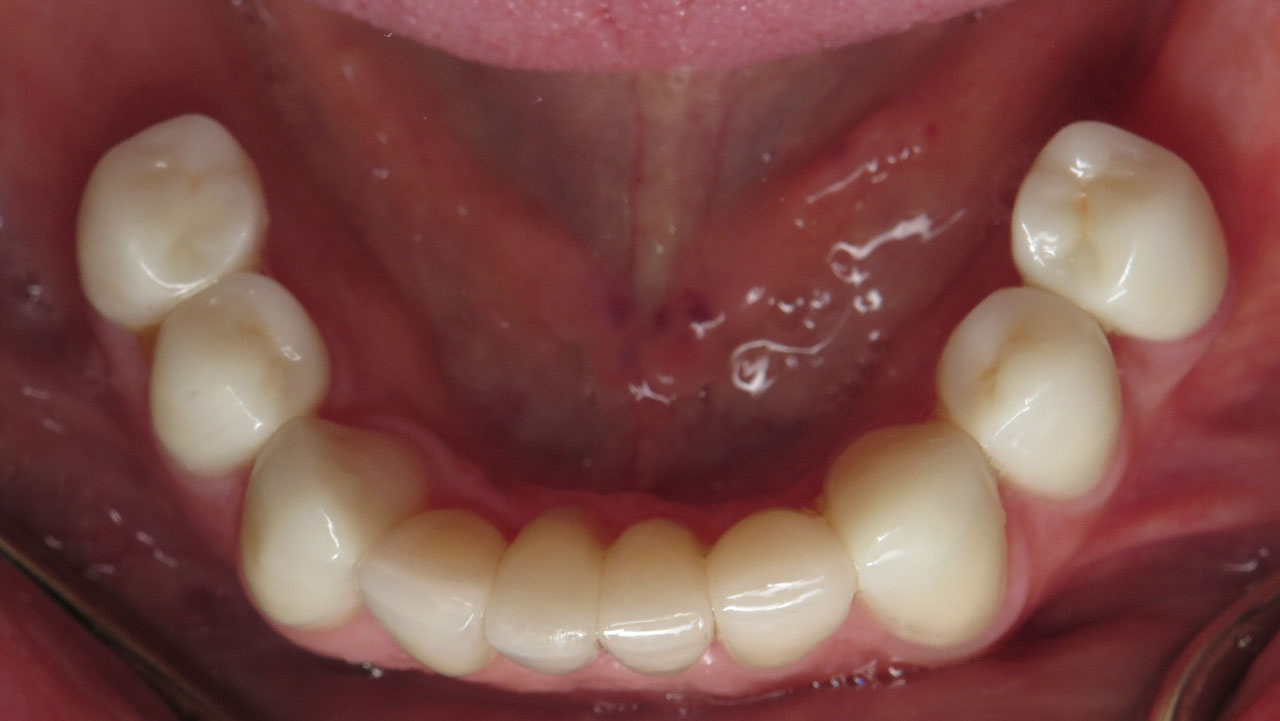

Hopeless lower teeth were removed and the remaining teeth were restored with all-ceramic crowns to rebuild the bite and protect the worn dentition.

- Full mouth rehabilitation with all-ceramic crowns

- Bite reconstruction to restore lost tooth structure

Treatment was completed in stages. The upper teeth were restored first with all-ceramic crowns to rebuild the bite. After a pause to allow the patient time for physical and financial recovery, treatment continued with restoration of the lower teeth.

The result is a stable bite that protects the remaining teeth and restores comfortable chewing.